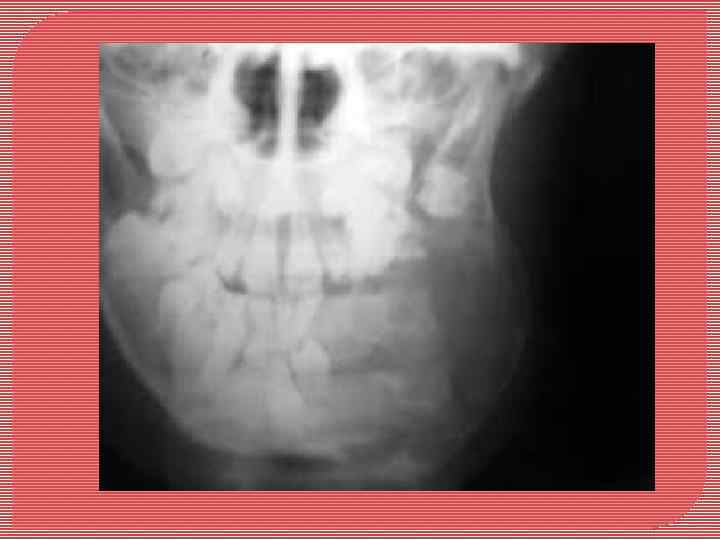

Остеома - доброкачественная костная опухоль. Чаще возникает у женщин молодого и среднего возраста. Характеризуется медленным ростом. Локализация: челюстные и другие кости черепа. Выделяют центральную и периферическую остеому. Центральная остеома развивается из эндооста, периферическая - из периоста. Периферическая остеома макроскопически округлой или неправильной формы, консистенции костной плотности, соединена с челюстью широким или узким основанием. Размер опухоли чаще всего от 1 до 2 см. При больших размерах может вызывать деформацию лица. Центральная остеома макроскопически располагается в глубине челюстной кости, небольших размеров до 1, 5 см, кортикальный слой не разрушается. Микроскопически остеомы делят на губчатые и компактные

Остеома верхней челюсти. Опухоль располагается в верхнечелюстной пазухе и полости носа (рентгенограмма)

Остеома нижней челюсти (рентгенограмма). Опухоль располагается в области угла.